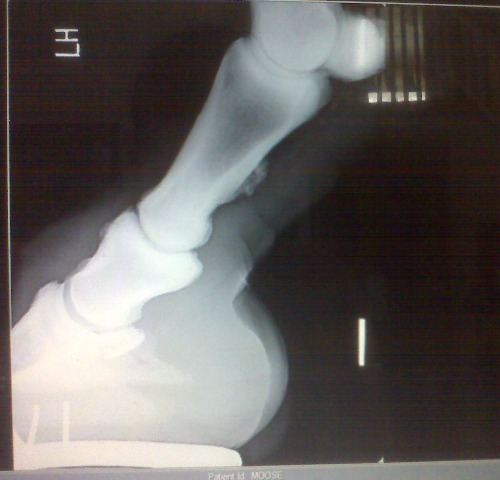

Posted on Sunday, Jun 27, 2010 - 10:00 am: Here are his x-rays that were taken 9/2007. It looks like references I have looked up as ringbone, what do you think?![]() ![]() ![]()

Posted on Tuesday, Jun 29, 2010 - 1:45 pm: Talk about a picture being worth a thousands words! Melissa your horse is not suffering so much from sidebone but has ringbone. This is a periostitis of the bones of the pastern that is spreading into the pastern joint (osteoarthritis) as evidenced by the osteophytes on the distal long pastern bone and proximal short pastern bone. By all means review the article on ringbone at HorseAdvice.com » Diseases of Horses » Lameness » Diseases of the Lower Limb » Ringbone. If you have questions following the article come back you can post them there and I will move this discussion into your post for continuities sake.DrO |